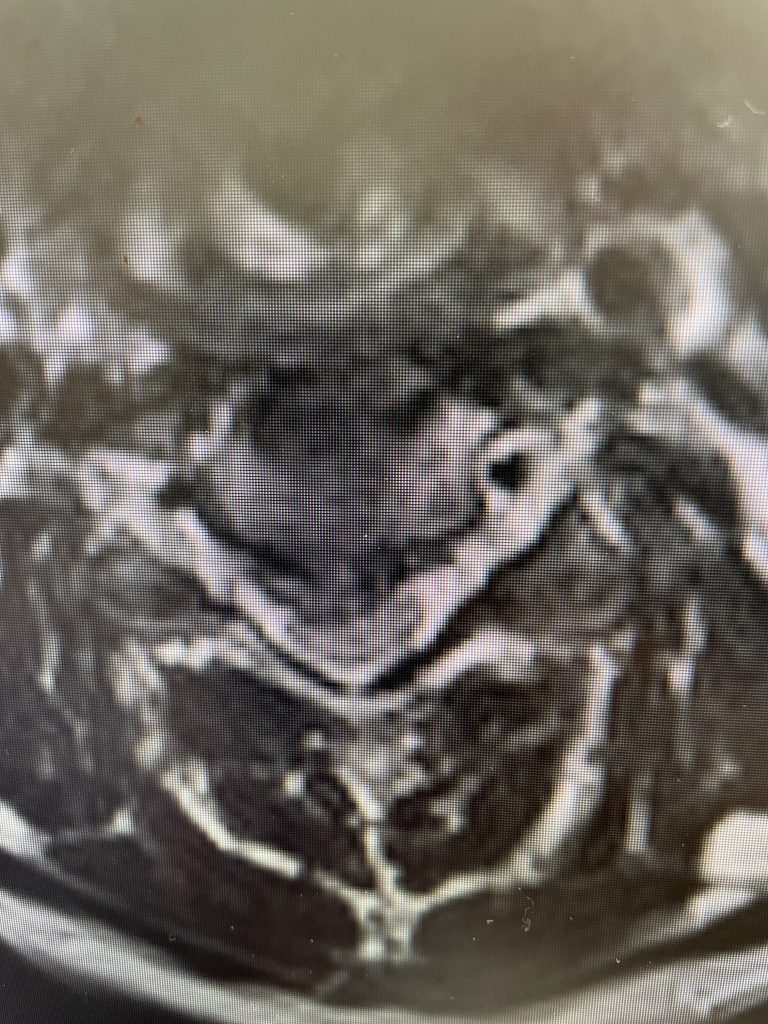

This 52 year-old female presents with 4 months of progressive neck pain, numbness of both hands, and difficulty using her hands and buttoning a shirt. She was noted to have mild right-sided weakness in a long track distribution which included her finger extensor, hip flexor, dorsiflexor weakness. She had tried chiropractic care. Imaging revealed a very large C4-5 disc herniation with severe cord compression which was more eccentric to the right, but also causing left-sided compression (Fig 1). The patient also had C5-6 disc collapse with biomechanical reduction of the C5-6 motion segment which puts more stress on the next segment. In essence the C5-6 is acting like it is autofused. This resulted in premature degeneration of the C4-5 segment which resulted in the disc herniation. It was decided, given a diagnosis of early cervical myelopathy with spinal cord compression, to offer an anterior cervical discectomy and fusion at C4-5 to decompress the spinal cord.